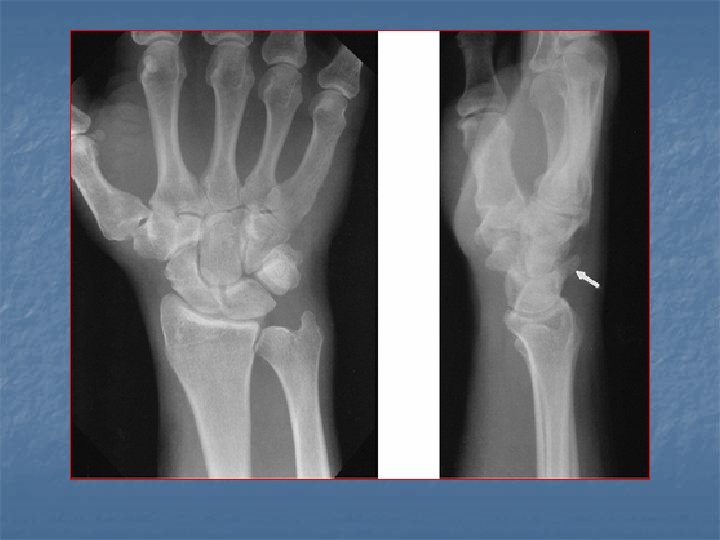

Lunate dislocation n On lateral view Axis of lunate is titled away from the articular surface of radius (spilled tea cup sign) n Capitate remains in normal alignment with radius and 3 rd metacarpal n n On dorsovolar view n Disruption of arc II while arc III remains intact